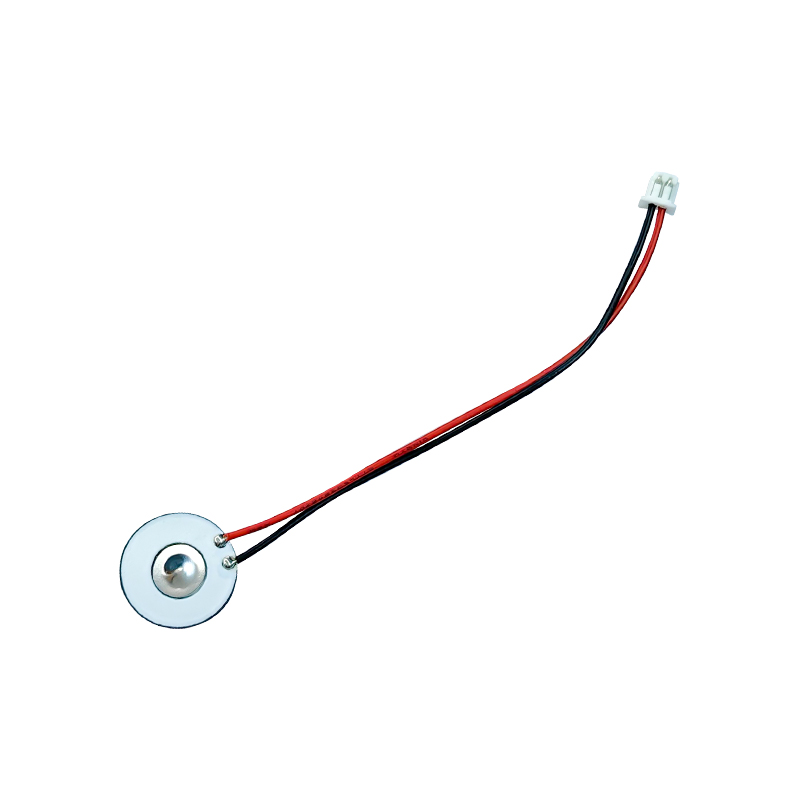

Les comprimés de nébuliseur à mailles médicales sont des composants de précision utilisés dans les dispositifs médicaux pour convertir des médicaments ou des solutions en minuscules particules d'aérosol pour le traitement de divers troubles respiratoires tels que l'asthme et la maladie pulmonaire obstructive chronique (MPOC), etc. par inhalation. La conception et le choix des matériaux de la feuille du nébuliseur sont essentiels pour garantir une administration efficace du médicament et le confort du patient. La feuille de diaphragme en acier inoxydable est percée de milliers de minuscules trous de maille de 2 à 3 µm dans la tôle d'acier grâce à une technologie de perçage laser dans un processus laser de précision, puis elle est étroitement liée à la feuille ronde en céramique piézoélectrique, qui convertit la fréquence de résonance de la feuille piézoélectrique en énergie de vibration haute fréquence via le signal de sortie de la carte de commande PCB, et décompose rapidement le médicament liquide en fines particules d'aérosol. Ces gouttelettes sont également appelées taille médiane des particules. Lorsque le pourcentage médian de la taille des particules D50 atteint > 60 % ou plus, les particules seront suffisamment petites pour pouvoir atteindre profondément les poumons jusqu'à la surface des alvéoles avec la respiration, améliorant ainsi l'efficacité d'absorption du médicament et l'effet thérapeutique. La feuille de nébuliseur à micro-mailles médicales a principalement plusieurs formes, une feuille de nébuliseur à micro-mailles en acier inoxydable, une feuille de nébuliseur médical en nickel palladium, une feuille de nébuliseur médical en polymère PI, etc. Tout ce qui précède se fait grâce à la conversion d'énergie de vibration piézoélectrique en céramique pour obtenir l'effet d'atomisation.

La céramique piézoélectrique sans plomb est connue sous le nom de « perle » de l'industrie piézoélectrique. L'avenir remplacera progressivement la céramique piézoélectrique à base de plomb sous tous ses aspects, qui a déjà les mêmes performances piézoélectriques, et la feuille piézoélectrique à base de plomb. Il est totalement non toxique, inoffensif, sûr et respectueux de l'environnement, ne contient pas de plomb, d'antimoine et d'autres métaux lourds et autres éléments restreints par Rohs, température de Curie élevée Tc-328 ° C, très faible perte électrique TangentLoss Par conséquent, la puce d'atomisation médicale piézoélectrique sans plomb a une grande valeur commerciale et une valeur universelle, des céramiques piézoélectriques véritablement non toxiques et respectueuses de l'environnement, sans plomb, en plus de performances piézoélectriques non polluantes comparables à celles des céramiques à base de plomb, deviendront une céramique piézoélectrique respectueuse de l'environnement populaire. Après des années de recherche et de développement, après des tests et des expérimentations continus, la société a réussi à fabriquer la puce d'atomisation médicale sans plomb pour atteindre le même niveau d'atomisation que la puce d'atomisation à base de plomb et les mêmes exigences en matière de particules de diamètre. La puce de nébuliseur Mesh médical sans plomb brillera sûrement et obtiendra un large éventail de scénarios d'utilisation.

L'atomiseur à ultrasons est un appareil qui utilise le principe de vibration ultrasonique (conversion d'énergie) pour convertir le liquide en minuscules gouttelettes. Le principe de fonctionnement est que les propriétés piézoélectriques uniques de la céramique piézoélectrique de la décision, la pièce d'atomisation à la réception de l'excitation du signal de champ électrique correspondant, produira la fréquence d'oscillation correspondante, grâce au rôle de vibration à haute fréquence de la cavitation liquide rejetée de la surface de l'eau pour produire une sorte de particules de brouillard d'eau, atomisées avec un grand nombre d'ions négatifs et de petites particules de molécules, peuvent réaliser une augmentation de l'humidité ambiante, le rôle de l'air frais. La surface de l'atomiseur est recouverte d'émail vitreux à une température élevée de 800 degrés pour protéger les électrodes d'argent de la feuille piézoélectrique, augmenter la résistance aux acides et aux alcalis et la résistance à l'oxydation de l'atomiseur et augmenter la durée de vie de l'atomiseur. Largement utilisé dans les humidificateurs d'intérieur, les purificateurs d'air, le traitement par nébuliseur médical et les voitures de beauté, par exemple dans d'autres domaines, mais convient également aux entrepôts, aux usines, à l'humidification, à la désinfection, pour créer l'atmosphère des équipements d'humidification. Les comprimés de brumisation sont principalement utilisés dans l'humidification industrielle, la brumisation médicale, la brumisation d'aromathérapie, l'humidification environnementale, la brumisation de jardin et d'autres scènes.